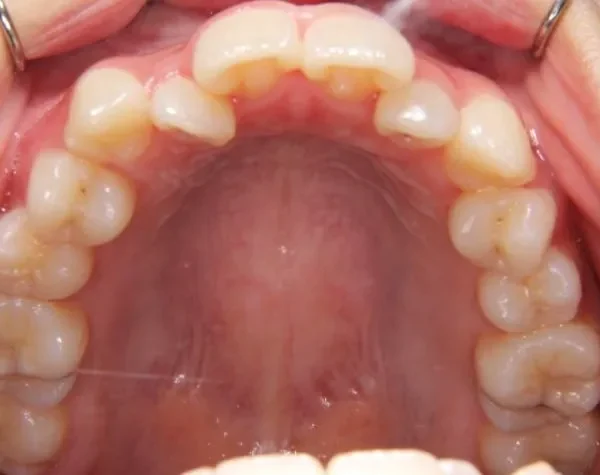

初診時年齢 高校生 (女性) 主訴 歯並びがガタガタ・口元の突出感

診断名 叢生・開咬・上下顎前突 装置名

状態 ガタガタ・でこぼこに生えている(叢生)

上下前歯、口元が出ている、口ゴボ(上下顎前突)

ガタガタの歯並びにお悩みの患者様でした。

口唇の突出感の他、下顎面高が長い印象も認められました。

歯科矯正アンカースクリューを用いた治療で、非抜歯で口唇突出の改善、臼歯の圧下、叢生の解消を図りました。